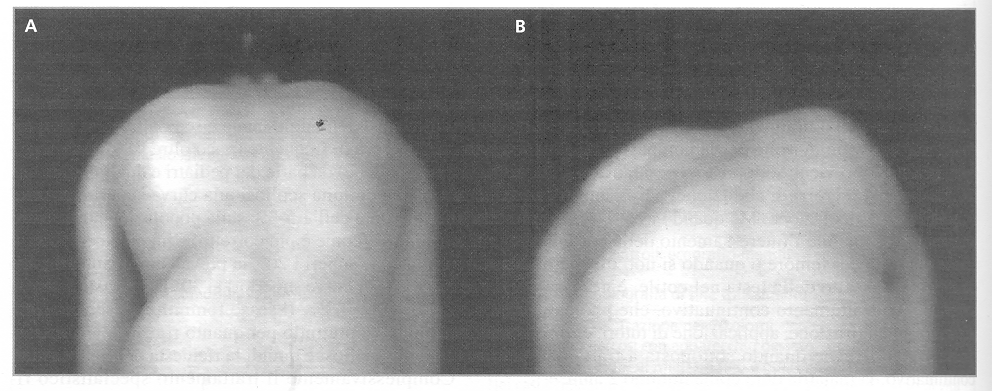

Figura

3. Assetto delle coste nella scoliosi strutturata (G. Bartolozzi,

Gugliemi M. Pediatria, Principi e pratica clinica, Elsevier

2008, pag. 1233)

Nonostante

tanti studi non è stato identificato nessun gene in

particolare: l'ipotesi più probabile è che si tratti

di una malattia che interessi numerosi geni, con particolari

prevalenze in alcune famiglie. La SIA progressiva viene attribuita a

una relativa crescita aumentata della colonna anteriormente, durante

il rapido accrescimento puberale. Studi con la risonanza magnetica

della morfometria vertebrale mostrano che la crescita longitudinale

dei corpi vertebrali in pazienti con SIA è sproporzionata e

più veloce che nei controlli della stessa età e dello

stesso sesso: essa ha luogo principalmente per ossificazione

encondrale. Al contrario la crescita della circonferenza in seguito

alla ossificazione membranosa è più lenta sia nei corpi

vertebrali che nei pedicelli dell'arco vertebrale (Figura

3). Ricordo che l'ossificazione può essere encondrale

(tutte le ossa fuorché clavicola e ossa craniche) e membranosa

(ossa craniche, clavicola e aumento della circonferenza delle altre

ossa).